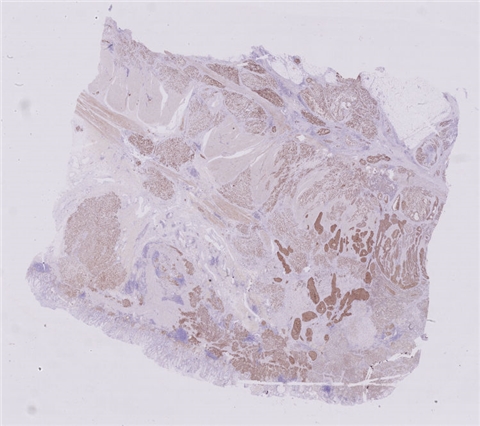

患者详情: 患者于半年前无明显诱因出现大便带血,为暗红色血便,未见粘液脓血便,反复发作,无腹痛腹胀,伴大便次数增多,并大便不成形,逐渐变细,初未引起重视,亦未行相应治疗,后症状逐渐加重。为进一步诊治,2020年3月入住我院。 直肠指诊:括约肌紧张度:正常,狭窄:无,触痛:无,距离肛门口大约4cm可及一环直肠一周肿块,质硬,移动度差,无压痛,指尖稍可通过肿块,指套染血:有。 电子肠镜示:距肛门4cm直肠处可见一巨大新生物,中间凹陷,底覆污秽苔,环2/3腔生长,钳取6块送病理,余 结肠各段粘膜光整,血管纹理清晰,未见明显的溃疡、息肉。 活检病理示:恶性肿瘤。后行腹腔镜直肠癌根治术。

大体所见: 1、直肠癌肿物:已切开肠管一段,长10cm,一侧切缘周长4cm,另一侧切缘已缝合,长3cm,紧邻缝合切缘见一溃疡型肿物,大小4.5*4*3cm,肿物切面灰白灰黄色、质硬,与周围组织分界欠清,侵及全层。

2、上切缘:灰褐色黏膜组织一块,大小1*1*0.4cm。

3、下切缘:灰褐色黏膜组织一块,大小1.2*1*0.4cm。

免疫组化: 2002032-004#:CgA(弱+)、syn(+)、CD56(+)、 2002032-002#:CK(+)、TTF-1(+)、CD34 +、SMA(-)

医院: 赣南医学院第一附属医院